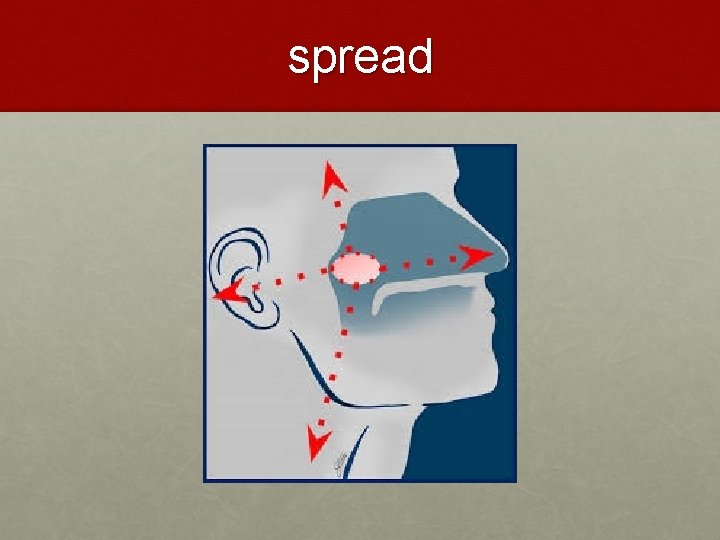

spread

Cervical Lymphadenopathy (60%) • tendency for early lymphatic spread • commonest palpable node – jugulodiagastric • contralateral lymph nodes metastasis (nasopharynx is midline structure) 35

Aural Symptoms • NPC leads to eustachian tube occlusion ü sensation of a blocked ear ü impaired hearing ü tinnitus ü u/l serous otitis media 36

Epistaxis and Nasorespiratory Symptoms • blood stained nasal discharge • profuse epistaxis • nasal obstruction • Hyponasal speech 37

Neurological Palsies • Most frequently involved are: ü VI - Lateral rectus palsy - Diplopia & squint ü III, IV, VI - are commonly affected together (opthalmoplegia) ü V – Facial pain & paraesthesia ü IX, X & XI - Jugular Foramen Syndrome (involvement of the IX, X, and XI CN) • Isolated single C. N. palsy common with nerves V & VI • Horner’s syndrome 38